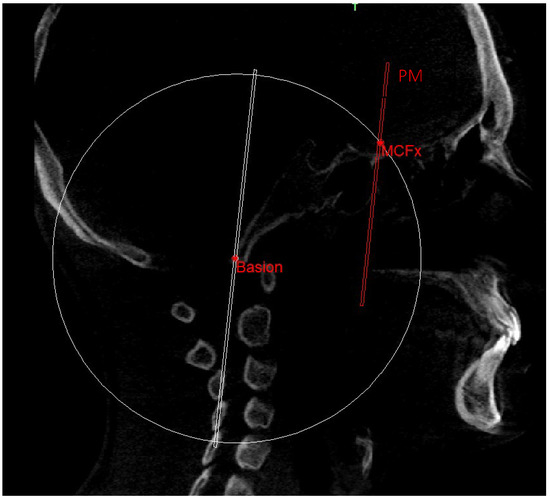

- PM (Figure 4) was identified by the points lMCF, rMCF and posterior nasal spine (PNS);

| Middle cranial floor, right side (rMCF) | Point in superior and endocranial surface where greater wings of sphenoid cross anterior cranial floor at posterolateral bony wall of right orbit | Anterior-most point of middle cranial floor (endocranial surface of greater wings of the sphenoid), right side | Point in endocranial surface where greater wing of sphenoid crosses anterior cranial floor at lateral bony wall of right orbit |

| Middle cranial floor, left side (lMCF) | Point in superior and endocranial surface where greater wings of sphenoid cross anterior cranial floor at posterolateral bony wall of left orbit | Anterior-most point of middle cranial floor (endocranial surface of greater wings of the sphenoid), left side | Point in endocranial surface where greater wing of sphenoid crosses anterior cranial floor at lateral bony wall of left orbit |

| Basion (Ba) | Most anterior point of foramen magnum | Most anterior point of foramen magnum | Most anterior point of foramen magnum |

| Middle point MCF (MCFx) | / | Point of intersection between the plane on which the Ba lies and a line joining the left and right MCF | / |